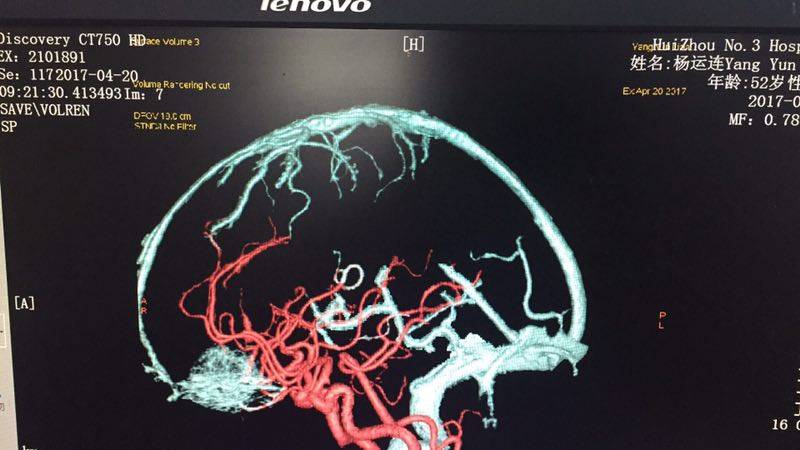

術(shù)前三維血管重建

3D打印技術(shù)下,醫(yī)生發(fā)現(xiàn)該腫瘤位于前顱底,經(jīng)過(guò)綜合考量及討論,最終決定采取微鎖孔手術(shù)入路,為病人設(shè)計(jì)了一例個(gè)性化的手術(shù),全稱(chēng) “右側(cè)經(jīng)眉弓鎖孔前顱底腫瘤切除術(shù)”。

基于病人基礎(chǔ)疾病多,臟器功能差,神經(jīng)外科李雪松主任帶領(lǐng)下的醫(yī)療團(tuán)隊(duì)制定了詳細(xì)的手術(shù)及診療方案,包括術(shù)前心電、血壓監(jiān)測(cè)及液體管理、手術(shù)風(fēng)險(xiǎn)及并發(fā)癥,術(shù)中借助電生理監(jiān)測(cè),保護(hù)周?chē)膭?dòng)脈和靜脈,術(shù)中、術(shù)后預(yù)防癲癇,保護(hù)功能殘留的腦細(xì)胞等。